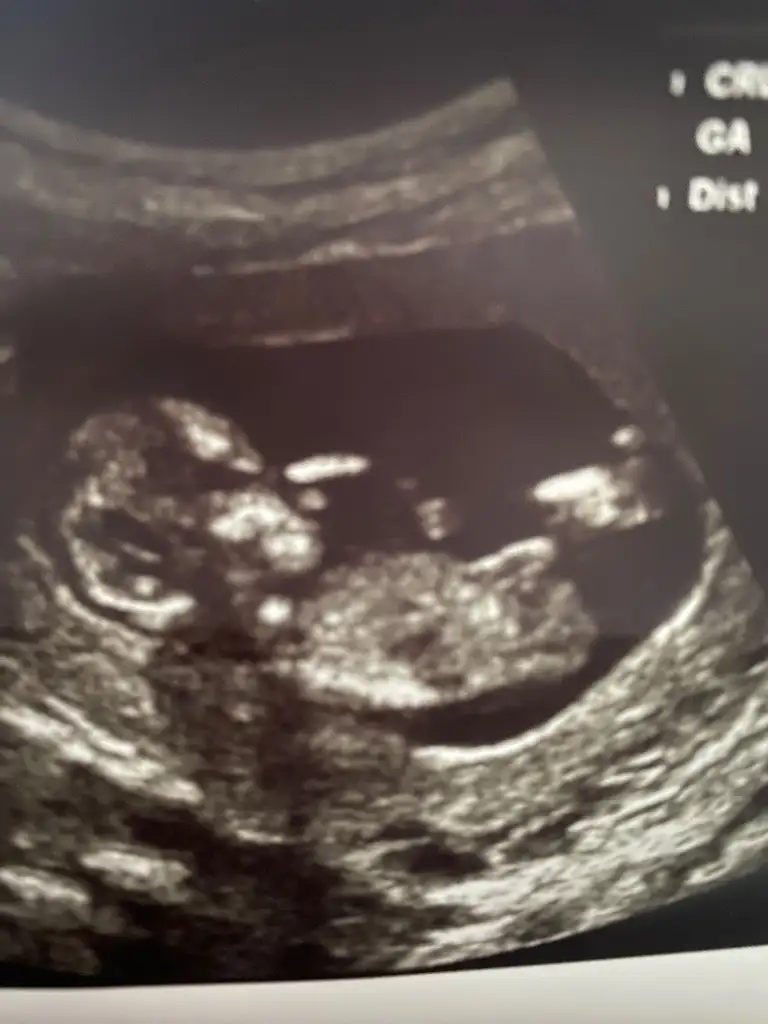

Bebeğin bulunduğu pozisyonda şu anlık belli olmuyor benceAnlıyorsaniz benimkinede bakar mısınız rica edersem

Bence kız doktor tahminde bulundu muMerhaba bnde tahmin alabilir miyim

Yok bulunmadı bidaha 18 inde gidicem bakalım inşallah öğrenirizBence kız doktor tahminde bulundu mu